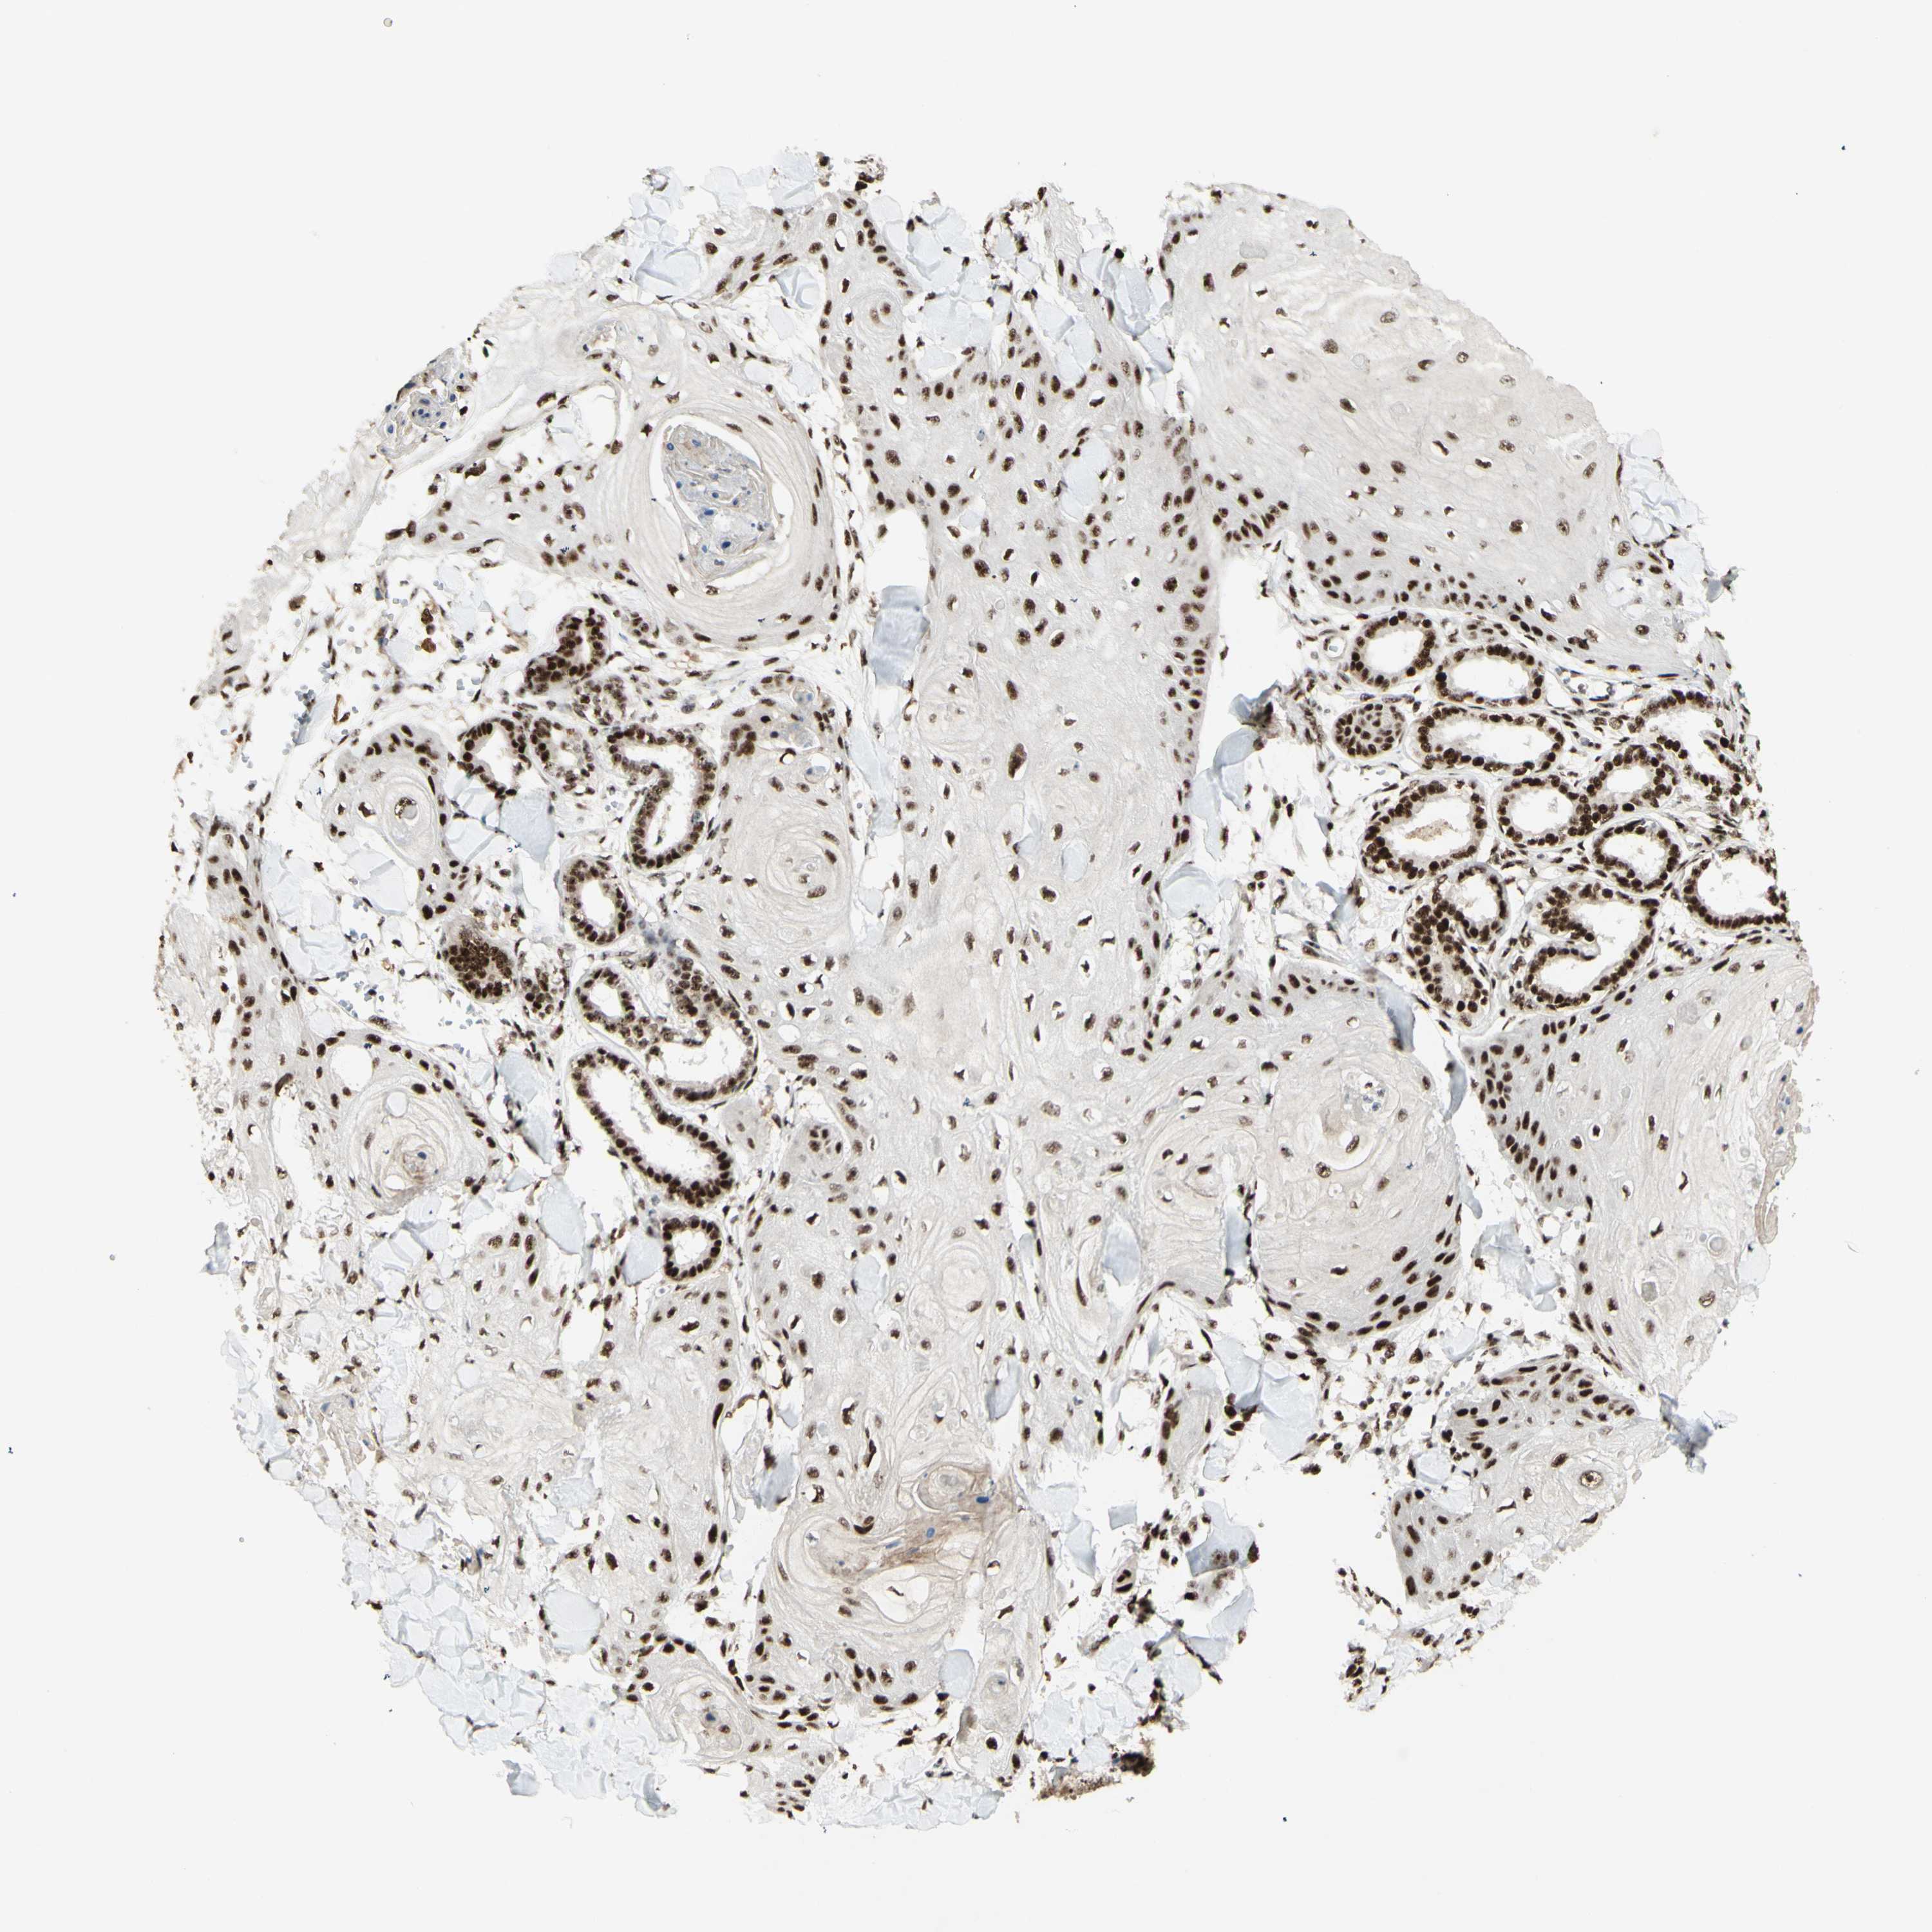

SKIN CANCER - Protein expressioni

A mouse-over function shows sample information and annotation data. Click on an image to view it in a full screen mode. Samples can be filtered based on level of antibody staining by selecting one or several of the following categories: high, medium, low and not detected. The assay and annotation is described here.

Each image is clickable and will lead to virtual microscopy that enables deeper exploration of all samples and also displays staining intensity scores, fraction scores and subcellular localization as well as patient and tissue information for each sample.

Antibody CAB011819

Medium

Intensity

Moderate

Quantity

75%-25%

Location

Nuclear

Adnexal tumor, benign